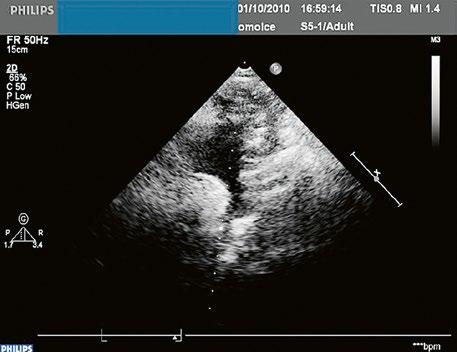

Echokardiografie a jícnová echokardiografie (TEE) je hlavní diagnostickou metodou se zhodnocením morfologie chlopně (Obr. 45.36, Obr. 45.37, Obr. 45.38, Obr. 45.39, Video 45.38), pravé komory (Obr. 45.44) i gradientu (Obr. 45.45). Samotný gradient může být při nevhodném úhlu podhodnocen a je třeba ho korelovat s gradientem na trikuspidální regurgitaci. V dospělosti může mít i významná PS nižší gradient při dysfunkční

Obr. 45.45 Těžká, dlouhodobě neřešená valvární a subvalvární stenóza plicnice s vysokým gradientem 155/82 mmHg (CW doppler) (viz též Obr. 45.44)